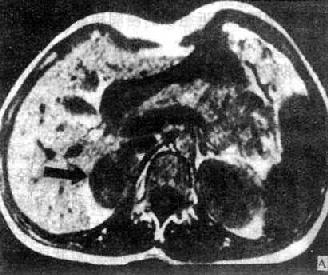

(二)肾上腺皮质腺瘤 肾上腺皮质腺瘤CT可见边缘光滑、圆形或椭圆形肿瘤,密度均匀,等于或低于肾的密度。增强扫描有均一强化。对侧肾上腺萎缩变小,但也可正常。肾上腺皮质瘤因分泌的激素性质不同,而有原发性醛固酮增多症和皮质醇增多症之分。前者腺瘤较小。约0.5~0.3cm。后者腺瘤较大,约2~8cm。均表现为圆形或椭圆形肿块。前者因瘤体小,常仅累及肾上腺的某一部分。两种功能性异常除腺瘤外也可因相应的肾上腺皮质增生所致。MRI腺瘤在T1和T2WI上信号强度与肝的信号相似或稍低于肝(图4-4-9)。

横断面

图4-4-9 右肾上腺腺瘤MRI(T1WI)